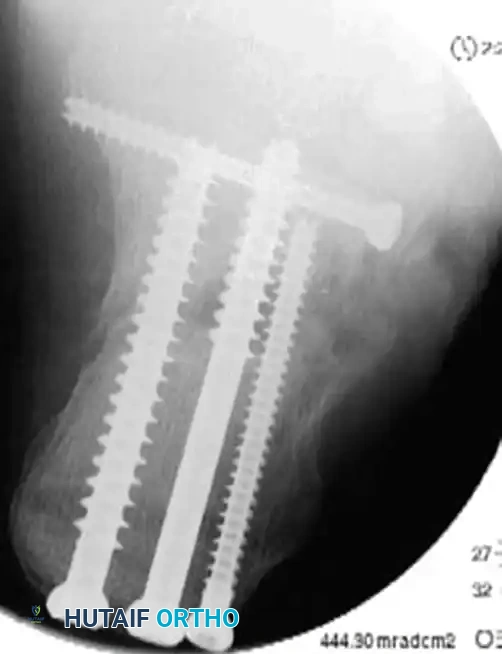

- Place 3.5-mm or 4.0-mm partially threaded cortical screws over the provisional K-wires. These screws are directed from lateral to medial, compressing the lateral articular fragment against the medial sustentacular fragment.

- To maintain the corrected position of the tuberosity, insert fully threaded screws from the posterior tuberosity directed anteriorly toward the calcaneocuboid joint, parallel to the initial Steinmann pin. Fully threaded screws are preferred here to act as position screws, preventing loss of calcaneal length.

- Perform a final fluoroscopic check to confirm extra-articular hardware placement, restoration of Böhler’s angle, and correction of varus alignment.